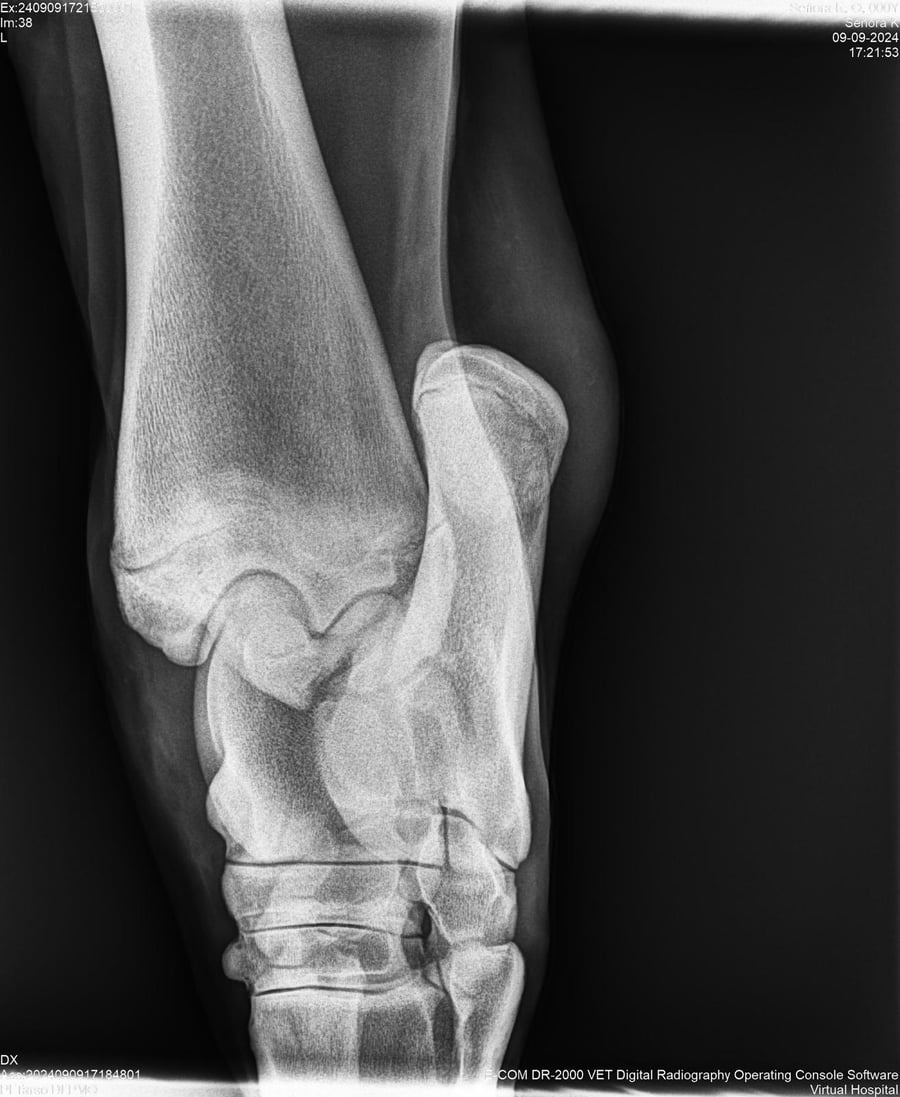

LOTE 44, SEÑORA K

Identificador: #291147-

Generacion 2022